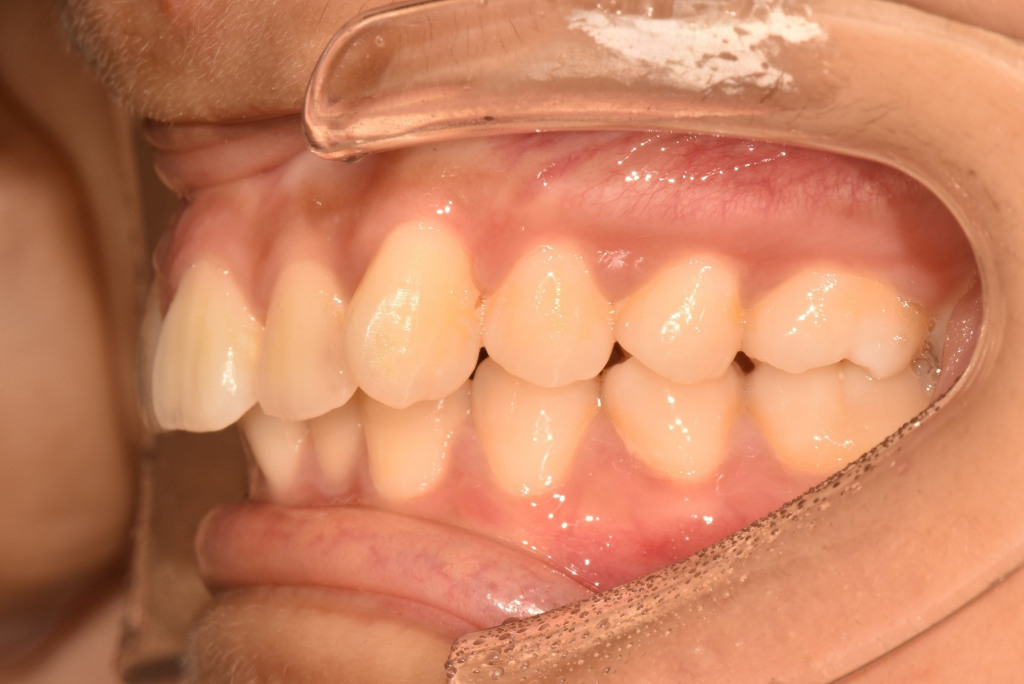

3. 정상교합과 비교해봤을 때 과개교합(deep bite)이 지금 아주 심한 상태는 아닙니다. 다만 위 치아가 아래 치아에 비해 전방 위치하고 있는데 이건 원인이 턱(위턱)때문인지 아니면 단순히 치아가 경사져서 그런지는 방사선 사진을 찍어봐야 판단이 내려집니다.

5. 제1대구치(첫번째 큰 어금니, 6번 치아)를 기준으로 class I, division 1의 부정교합 상태인 것 같은데 작은 어금니 발치를 통해 위 앞니를 조금 밀어 넣고, 제1대구치도 교합이 맞게 위치를 조정하게 될 것으로 보입니다.